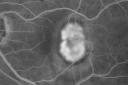

CNVM - Subfoveal Classic - Old Toxoplasmosis Scar Right Eye

OD: Vertical C/D ratio is 0.3. There is no posterior vitreous separation. There is a large macular scar with exudate at the edges. It is centered superotemporal to the macula, but it involves the center of the fovea.

FLUORESCEIN ANGIOGRAPHY: Fluorescein angiography of the left eye shows a classic subfoveal choroidal neovascular membrane 2 disc areas in size. The right eye shows a large hyperfluorescence macular scar with leakage at the edge.